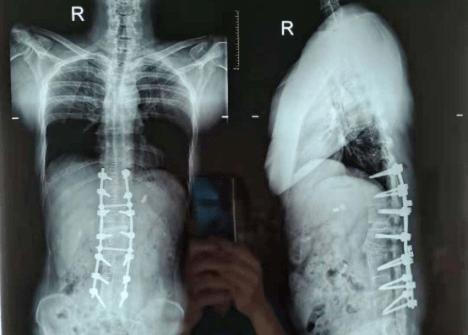

医院新闻脊柱外科专家妙手拉直折刀人